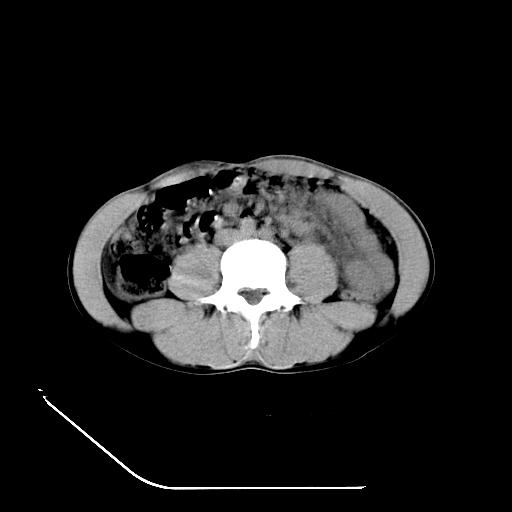

m-25y 高空堕落 12 月5号

12月7号病人尿量200ml/24h 急查双肾ct

左肾挫裂伤并肾周血肿;

肝肾间隙可见液区,建议手术探查;

支持:1、左肾挫裂伤并肾周血肿;

2、少量腹水;

3、左肾旋转不良;

4、反射性肠淤张。

除了1:左肾挫裂伤并肾周血肿;

2:少量腹水

第二次ct检查后:临床医生腹水穿刺后考虑肠系膜动脉破裂,后实行剖腹探查:于空肠距离十二指肠90cm处发现肠管破裂,破裂口较小;修补后关腹。